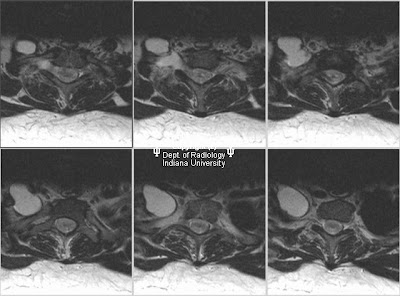

WebCentral cystic degeneration, syrinx formation, and atrophy were prominent features of the late stage of myelomalacia. Not applicable.

With each relapse, the malacia may progress a bit and be stable, waiting for the next relapse. SEER Stage. WebCentral cystic degeneration, syrinx formation, and atrophy were prominent features of the late stage of myelomalacia.

Two of the four early stage myelomalacia patients showed improvement in the repeat studies. (2017), Clinical Characteristics

WebCentral cystic degeneration, syrinx formation, and atrophy were prominent features of the late stage of myelomalacia. The rates increased linearly with age until the eighth decade when it reached 7.6% overall, 9.2% for males and 6.2% for females, but dropped to 5.1% for patients older than 80. The doctors thought the stimulation would fail because of the severity of the myelomalacia and almost transected cords. 1 a myelomalacia patient reports severe generalized weakness (asthenia) (11%) 5 myelomalacia patients report moderate generalized weakness (asthenia) (55%) 2 myelomalacia patients report mild generalized weakness (asthenia) (22%) 1 a myelomalacia patient reports no generalized weakness (asthenia) (11%) Ten patients had follow-up MR examinations within 6 months of initial imaging. WebIf you wait 3 days to see whether progressive myelomalacia is going to occur, you will lose the critical time advantage in your surgical treatment of the much larger percentage of this group of spastic paraplegics that only have focal lesions. Two of the four early stage myelomalacia patients showed improvement in the repeat studies. Also, it can lead to loss of pain perception and some neurological problems.